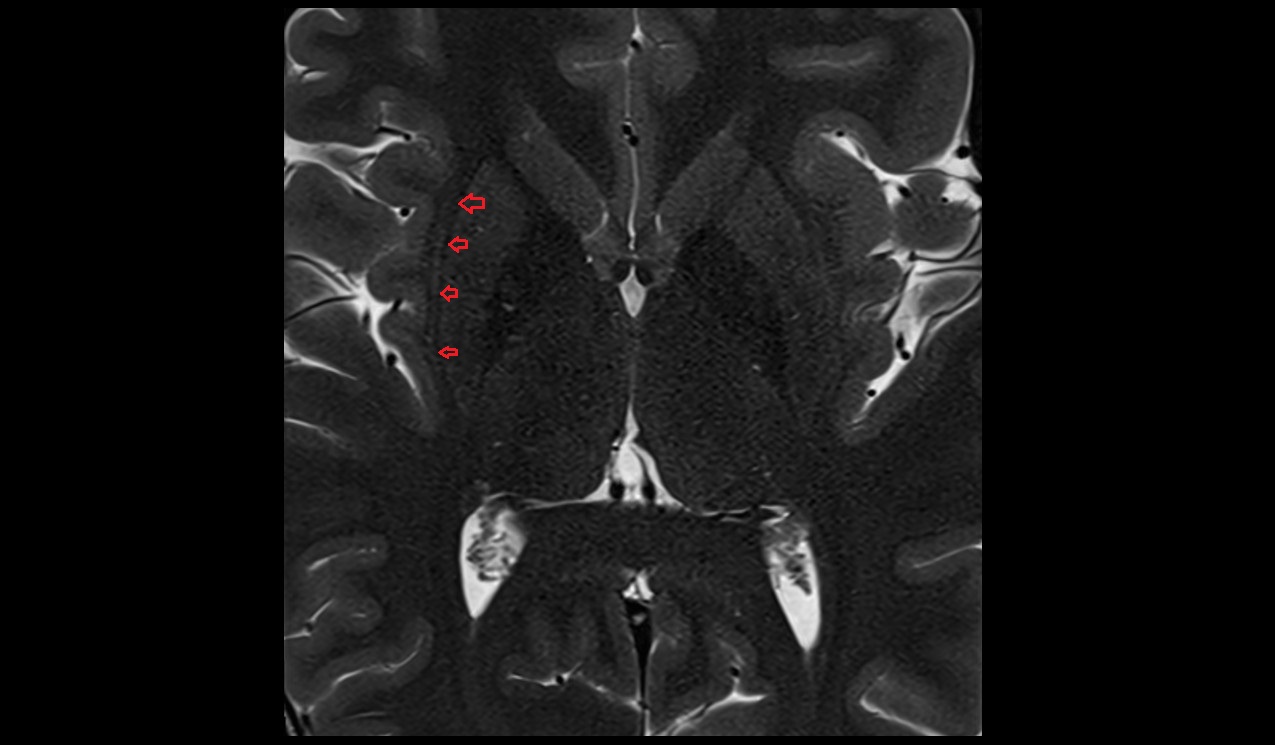

- Hippocampus